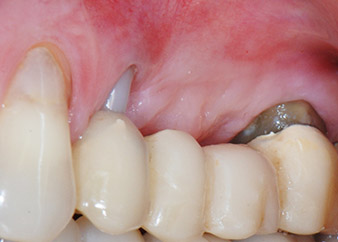

Una paziente donna di 58 anni lamentava dolore e aumentata mobilità del dente di appoggio del ponte 24. Era presente infiammazione periodontale con tasche di profondità di 7 mm a livello mesiobuccale e di più di 12 mm a livello distale, nonché coinvolgimento di terzo grado della forcazione. Inoltre, la radiografia rivelava una lesione periodontale estensiva attorno alla regione apicale del dente pretrattato 24 (in altro luogo) a livello endodontico (Fig. 1).

Un mese più tardi, nel giorno programmato per l'intervento, il dolore e l'infiammazione in corrispondenza del dente 24 erano minimi, ma era ancora presente mobilità di classe 2 secondo Miller. Dopo l'apertura dei lembi e la pulizia del tessuto periapicale e periradicolare infetto, l'estensione della mancanza ossea si è resa evidente (Figg. 2 e 3).

Tutto il tessuto osseo vestibolare e distale era mancante in corrispondenza della radice buccale. La possibilità di attacco era essenzialmente ristretta alla radice palatale, evidenziando la prognosi negativa preliminare. Anche il dente 27 mostrava un punto di attacco orizzontale ridotto e una rarefazione apicale minima (cfr. Fig. 1), senza sintomi clinici.